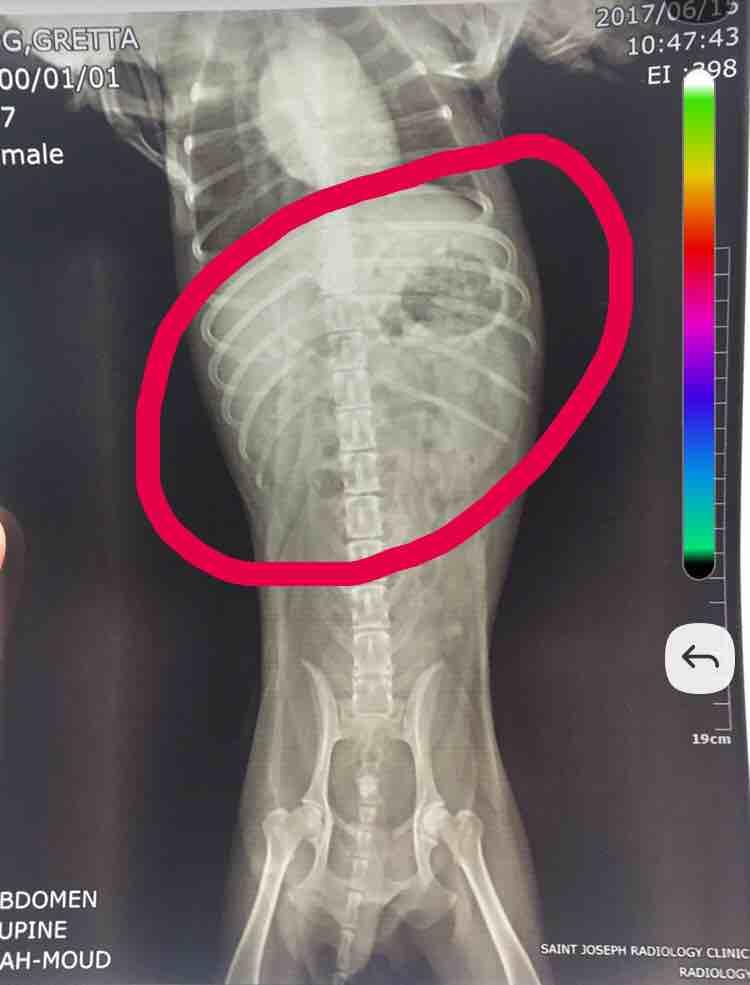

Hi. I just had my dog x-rayed again. I want to ask for your opinion regarding the encircled part of the xray.. do you think this is normal? I know theres a stone in the bladder but i'm curious about that thing i encircled.. my vet says its fine but im still curious. Is it just gas? Theres no other way to look closely because ultrasound is not available here in my city. Thanks

Unfortunately the quality of the image coming through to us isn't great. If you are talking about the circular area on the upper right side of the abdomen, this is gas in the stomach and can be normal. If your vet wants to try additional diagnostics but doesn't have ultrasound, they could do a barium study, or they could send the x-rays to a radiologist for review (a veterinary radiologist has extensive training at reviewing x-rays and so can sometimes interpret things a regular vet may not). X-rays can be send electronically to a radiologist for review through various services, so I would ask them if they feel either of these options would be appropriate.